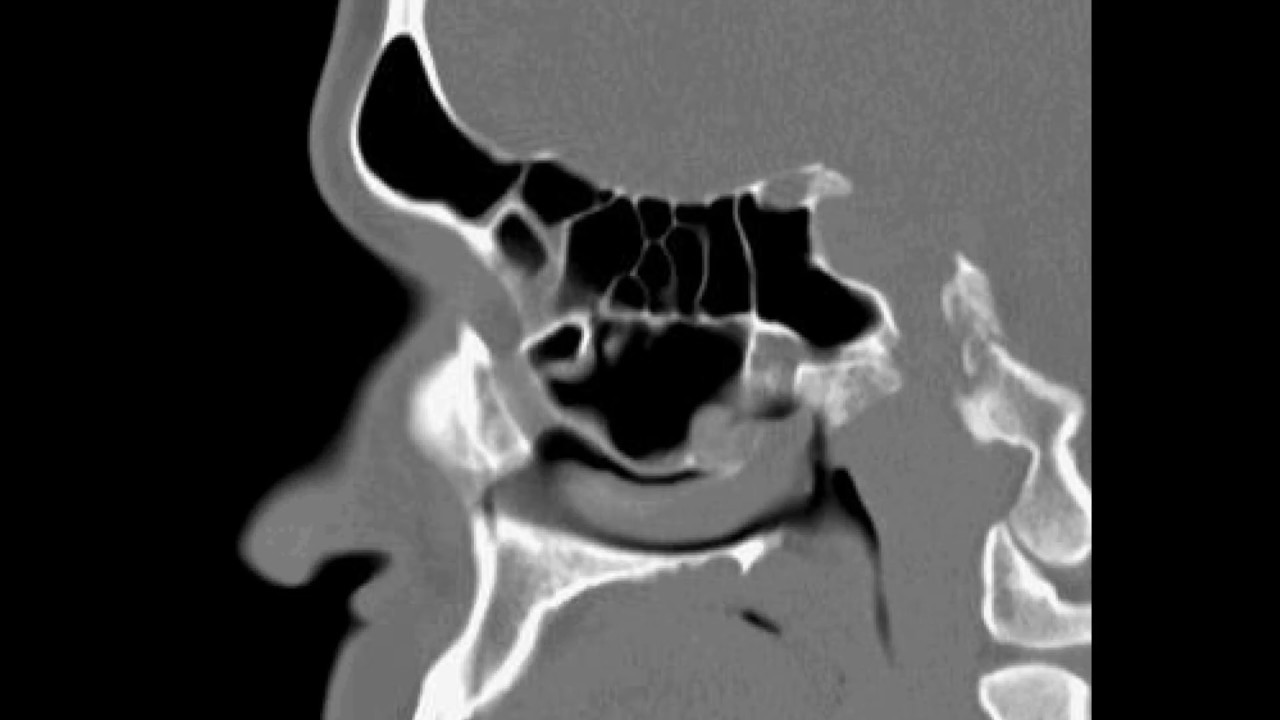

Pre Fess Pns Ct